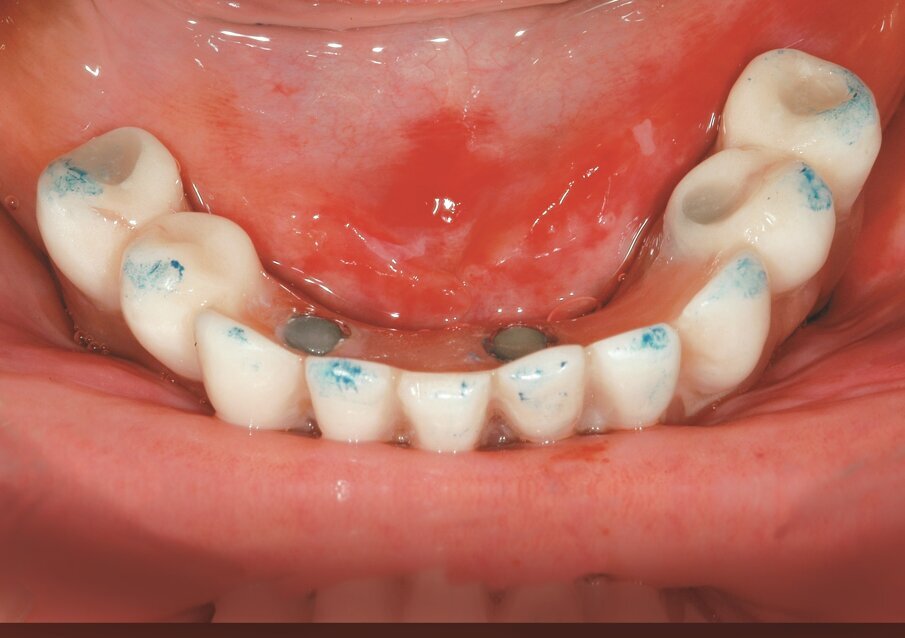

Fig. 2b_Fase protesica provvisoria. Corona provvisoria avvitata.

Fig. 2c_Fase protesica provvisoria libera da contatti occlusali.